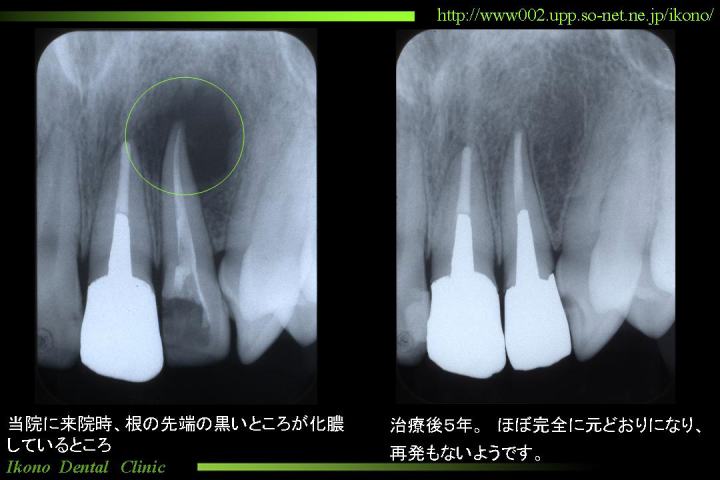

治療がうまく行かず、再発した場合、今度は歯の外側で、炎症(一般的に化膿していると説明される)が起こります。

こうなると噛んだら痛い、歯茎が腫れる、歯が浮いたような感じがするといった症状が出ます。

そうすると再治療が必要になりますが、再治療はさらに時間がかかるだけでなく、むずかしい治療になります。

当院の治療例クリックで拡大

歯内治療は患者さんにとって、見えないところにもかかわらず、時間や回数がかかり楽な治療ではありません。 けれども、なるべく再発しないよう、信頼できる歯科医で、最後までしっかり治療することが大切です。

また、治療したあとは再発していないか定期的にレントゲンで確認することをお勧めします。